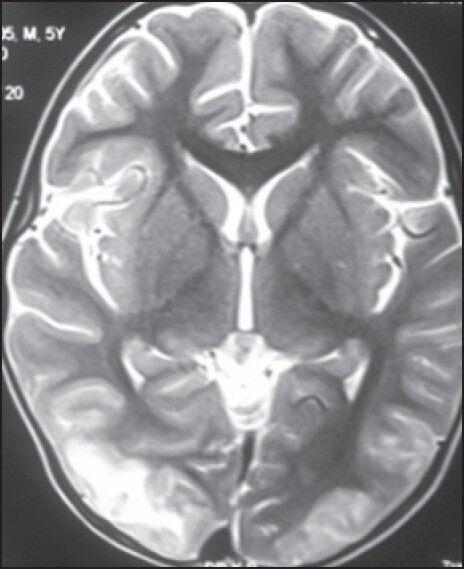

Posterior reversible encephalopathy syndrome (PRES) is a neurotoxic state coupled with a unique radio imaging appearance. We describe this rare, mostly reversible condition in five cases undergoing similar treatment under preset protocol (MCP-841) for acute lymphoblastic leukemia (ALL) at our centre. Hypertension is a well-known adverse effect of high-dose corticosteroid therapy primarily mediated by its effects on the mineralocorticoid receptor especially in pediatric population and we hypothesize that this may be the etiology of PRES in two of these patients.

后部可逆性脑病综合征(PRES)是一种伴有独特影像学表现的神经毒性状态。我们描述了在我们中心接受针对急性淋巴细胞白血病(ALL)的预设方案(MCP - 841)进行类似治疗的5例患者中出现的这种罕见且大多可逆的病症。高血压是高剂量糖皮质激素治疗的一种众所周知的不良反应,主要通过其对盐皮质激素受体的作用介导,尤其是在儿科人群中,我们推测这可能是其中2例患者发生PRES的病因。